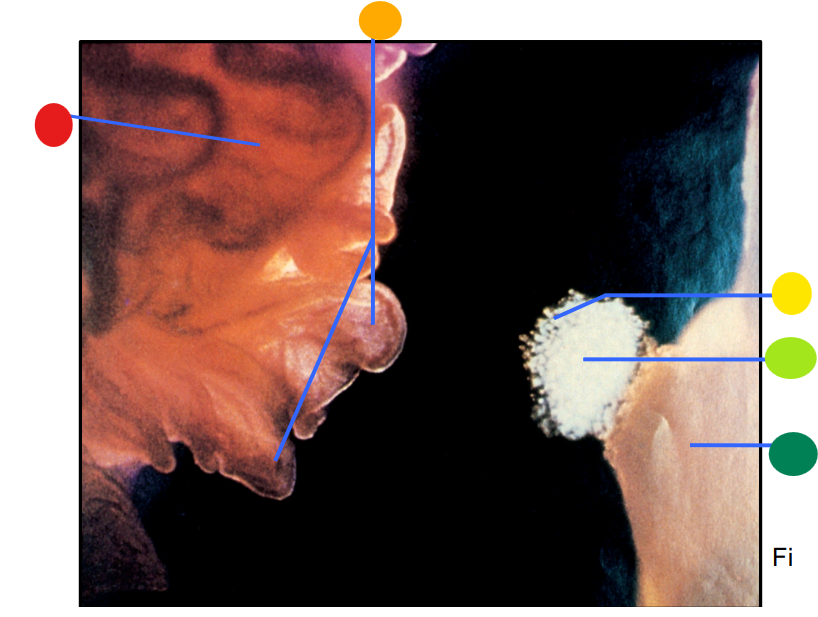

red

infundibulum

orange

fimbriae

yellow

cumulus oophorus

light green

oocyte

dark green

ovary

How is the egg and culmulus oophorus drawn into the infundibulum after the rupture of a mature follicle?

via ciliary action